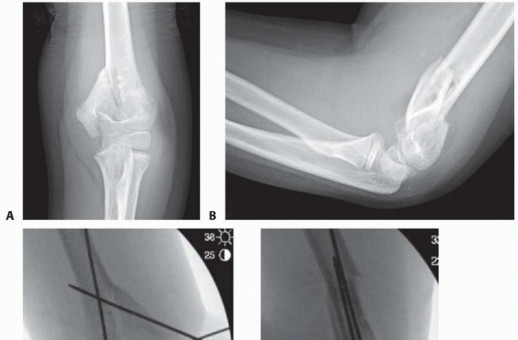

Chapter 13 Open Reduction and Internal Fixation of Pediatric T-Condylar Fractures Keith D. Baldwin John M. Fl…

Chapter 7 Open Reduction of Supracondylar Fractures of the Humerus Christine M. Goodbody John M. Flynn DEFINI…